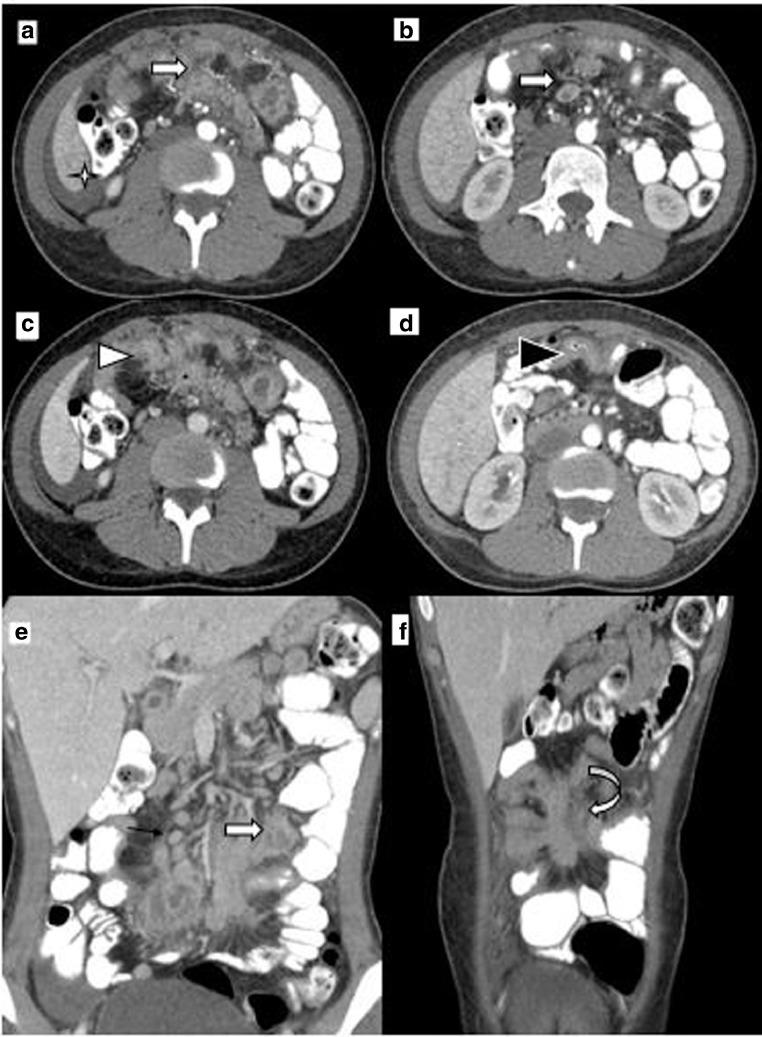

This article presents fibrosing mesenteric tuberculosis in a 19-year-old Arab boy who presented with weight loss, fever, abdominal pain, and distension. Abdominal contrast enhanced computed tomography (CECT) was performed which showed large infiltrative ill-defined mesenteric-based enhancing soft tissue phlegmonous mass with surrounding desmoplastic reaction causing retraction-kinking of small bowel loops associated with central necrotic mesenteric lymph nodes, multifocal small bowel wall thickening, and ascites. Abdominal tuberculosis is a diagnostic challenge particularly if pulmonary tuberculosis is absent as in this case. CT appears to be the modality of choice if clinical and epidemiological suspicion is high in order to ensure early treatment for a favorable outcome.

本文介绍了一名19岁阿拉伯男孩的纤维性肠系膜结核,该男孩出现体重减轻、发热、腹痛和腹胀症状。进行了腹部增强计算机断层扫描(CECT),结果显示有一个大的浸润性、边界不清、以肠系膜为基底的强化软组织蜂窝状肿块,周围有促纤维增生反应,导致小肠袢回缩扭结,伴有中央坏死的肠系膜淋巴结、多灶性小肠壁增厚和腹水。腹部结核是一个诊断难题,特别是在像本例这样没有肺结核的情况下。如果临床和流行病学怀疑度高,CT似乎是首选的检查方式,以确保早期治疗获得良好结果。